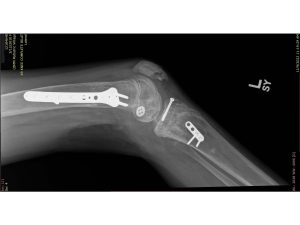

An 11-year-old McAuliffe Middle School student suffered severe orthopedic injuries to both lower extremities, significant emotional and psychological trauma, and permanent disability after she became pinned between two vehicles in the school parking lot during after-school pickup.